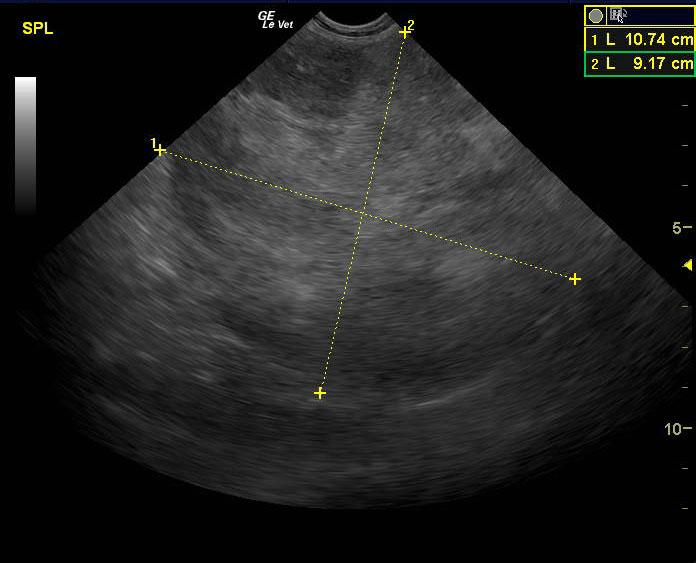

A 14-year-old SF Chow mix was presented for evaluation of weakness, which had also been present a week ago. On physical examination, a palpable abdominal mass was present. Severe non-regenerative anemia and hypoalbuminemia were present on CBC and blood chemistry.